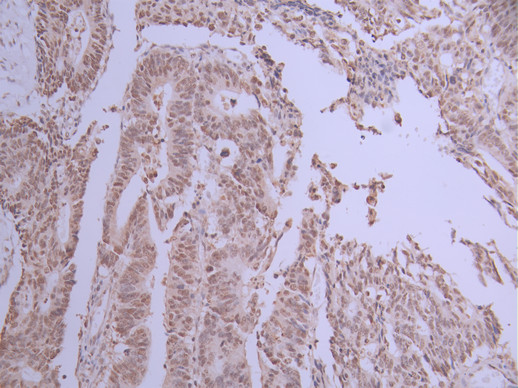

IHC image of CSB-RA967272A0HU diluted at 1:100 and staining in paraffin-embedded human colorectal cancer performed on a Leica BondTM system. After dewaxing and hydration, antigen retrieval was mediated by high pressure in a citrate buffer (pH 6.0). Section was blocked with 10% normal goat serum 30min at RT. Then primary antibody (1% BSA) was incubated at 4°C overnight. The primary is detected by a Goat anti-rabbit polymer IgG labeled by HRP and visualized using 0.05% DAB.